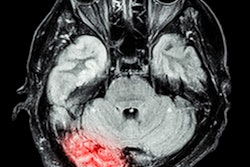

Cerebrovascular imaging software developer iSchemaView said that its Rapid neuroimaging software platform has now been installed at 520 stroke centers in 22 countries around the world. In addition, more than 55 other centers have committed to deploying the platform, according to the vendor.

The number of Rapid installations has increased by 48% since April, iSchemaView said. Rapid is also being used in six multicenter clinical trials around the world, adding 200 hospitals to the company's installed base.